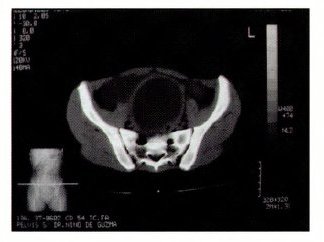

Fig: 4 TAC Hematometra y Hematocolpos

La paciente es operada con el diagnóstico de tabique vaginal transverso incompleto a pesar de no demostrarse solución de continuidad en la vagina. Los reportes ecográficos y TAC reportaron hematometra gigante con hematocolpos y presencia de posible tabique vaginal en 1/3 inferior de vagina, que coincide con el examen físico que mostraba un tabique vaginal completo (Fig: 1,2,3,4).

Tratada con el diagnóstico de tabique vaginal incompleto por el antecedente de perdida de escasa secreción achocolotada. Se solicita exámenes de laboratorio de rutina quirúrgica, además ecografía Ginecológica y TAC de pelvis, no se solicita ecografía transrectal por tener buenos resultados con la ecografía ginecológica.